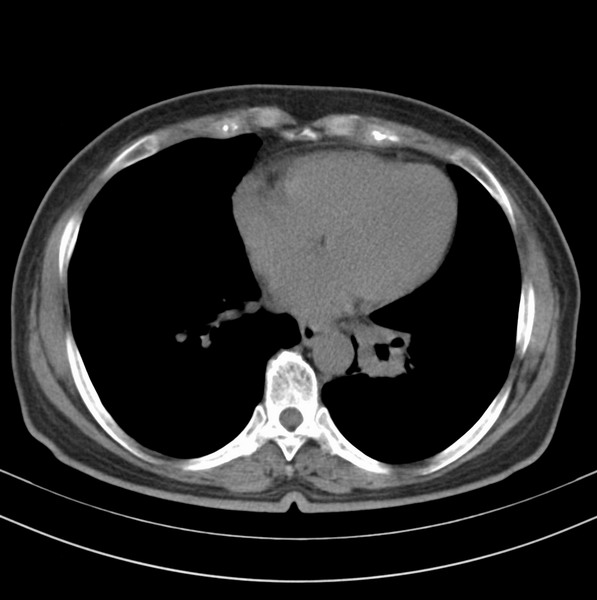

标题: CT20053:胸部增强请会诊。

女、63

咳嗽、胸痛四个月

包绕左下肺基底段的不规则的软组织肿块,段支气管腔变形、狭窄及阻塞性炎症,病变区不规则强化,又是老年女性支持楼上看法。

典型病例:左下肺基底段中央型肺癌,相应支气管狭窄并阻塞性炎症